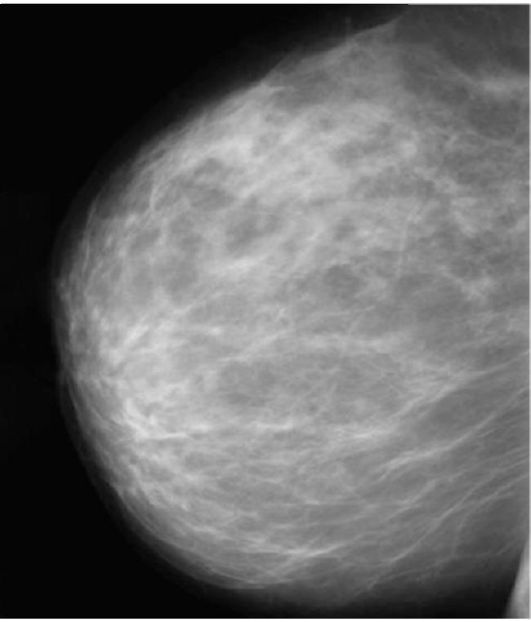

Что такое маммография: важность, процесс и результаты